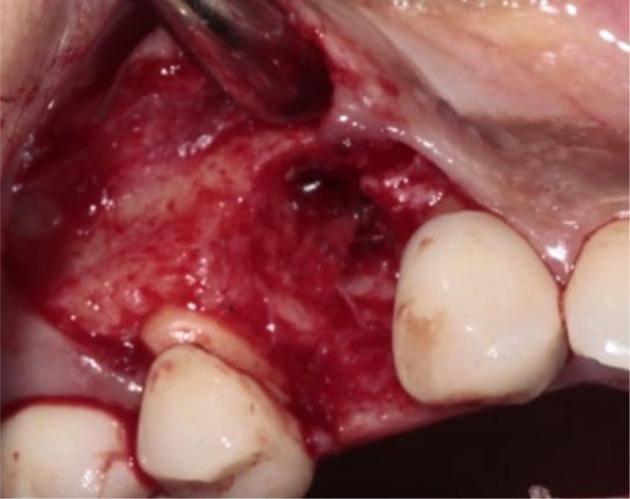

Peri-implantitis leads to gradual peri-implant bone loss. Severe and extreme cases lead to complete implant failure and imply lost implants have to be removed. Residual ridge deformity management after implant removal is one of the factors contributing to improved aesthetic and functional results. Various grafting procedures have been developed to achieve this goal. This report describes a case of implant removal from the upper right first premolar due to advanced peri-implantitis in a 51-year-old female patient. Guided bone regeneration with a alloplastic bone graft and resorbable collagen membrane combined with roll pedicle connective tissue graftt was used for both socket and soft-tissue augmentation. This was combined with ovate design conventional provisional bridge. After a 6-month of healing phase, a perfect adaptation of the marginal gingiva around the provisional restoration was obtained. Cone beam computed tomography revealed significant bone fill and buccolingual dimensional stability. A conventional all-ceramic bridge with an oval pontic design was chosen as a definitive prosthetic solution to compensate for edentulism and maintain the good aesthetic results. According to the encouraging result obtained in this clinical case, the conventional prosthetic restoration associated with surgical reconstruction of failing tissues can be considered as a successful treatment in the case of advanced peri-implantitis requiring implant removal.

种植体周围炎会导致种植体周围骨质逐渐流失。严重和极端的病例会导致种植体完全失败,意味着必须移除丢失的种植体。种植体移除后对剩余牙槽嵴畸形的处理是改善美学和功能效果的因素之一。已经开发了各种植骨手术来实现这一目标。本报告描述了一名51岁女性患者因严重种植体周围炎而拔除右上第一前磨牙种植体的病例。采用异体骨移植和可吸收胶原膜引导骨再生,并结合带蒂结缔组织瓣移植进行牙槽窝和软组织增量。这与卵形设计的传统临时桥体相结合。经过6个月的愈合期,临时修复体周围的边缘牙龈实现了完美贴合。锥形束计算机断层扫描显示骨填充显著且颊舌向尺寸稳定。选择了具有椭圆形桥体设计的传统全瓷桥作为最终修复方案,以弥补牙列缺失并保持良好的美学效果。根据该临床病例获得的令人鼓舞的结果,对于需要移除种植体的晚期种植体周围炎病例,与失败组织的手术重建相关的传统修复体可以被视为一种成功的治疗方法。